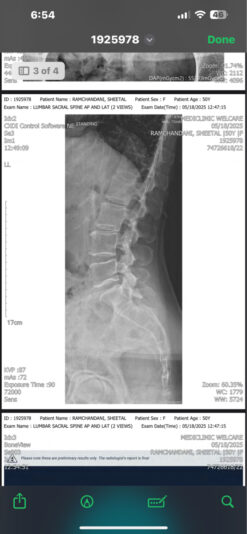

@Bernadette_Abraham my concern at this moment is lower back pain which has been on for a month ,

X-rays say no spine issues , discs or bulge but the lower back pain does not seem to reduce even after physiotherapy sessions , my reports as shared below seem fine as mentioned by the orthopedic doctors

attached is the xray report